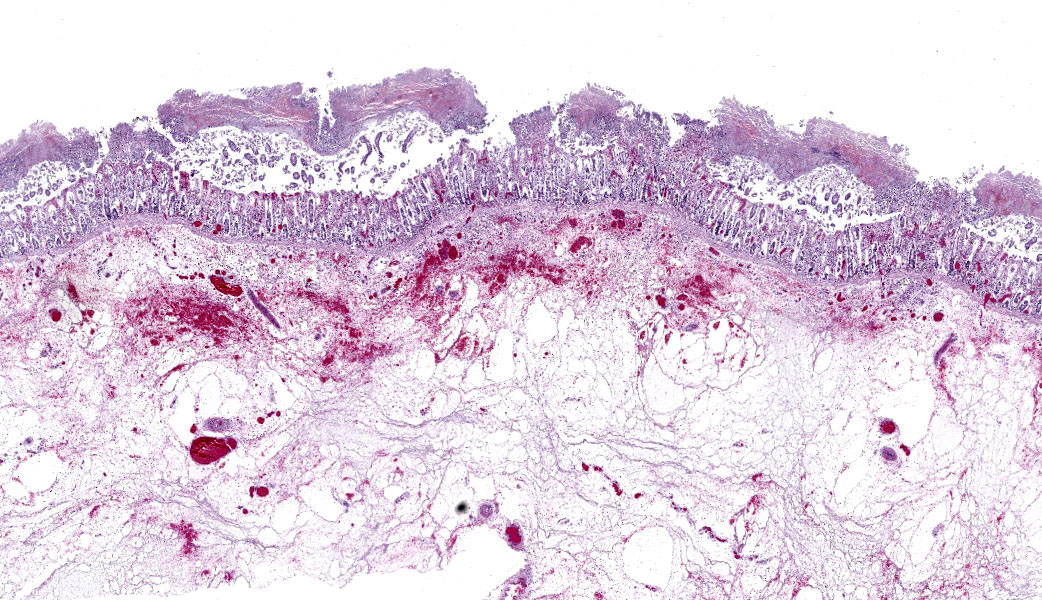

The carcass was in good nutritional condition, with adequate amount of fat reserves, well fleshed, moderately dehydrated, and mild to moderate state of postmortem decomposition.

About 10 liters of murky fluid were present in the abdomen. There were ~ 5 liters of clear thoracic fluid. The serosa of the colon was multifocally hemorrhagic. There was clear liquid content throughout small and large intestine, and a pseudo membrane covering the mucosa of the right ventral colon and cecum.

Colon: There is severe, diffuse necrosis of the mucosa where the superficial epithelium and, less prominently, the crypt epithelium is lost and/or show hypereosinophilia, pyknosis, karyorrhexis and karyolysis. The lamina propria is diffusely eosinophilic and infiltrated by a large number of viable and degenerated neutrophils and fewer neutrophils, plasma cells and macrophages; this cellular infiltration extends to the submucosa. Multifocally, the mucosa is covered by a thick pseudo membrane composed of fibrin, cell debris, red blood cells, neutrophils and myriad mixed bacteria. Several blood vessels of the lamina propria show thrombosis. In areas where the superficial epithelium is still present, erosions are seen through which large number of neutrophils are seen exiting the lamina propria into the lumen (volcano lesions). The submucosa is severely dilated and edematous; there is vascular congestion and the lymphatic vessels are dilated. The serosa shows reactive mesothelial cells.

Colitis, fibrinonecrotizing, diffuse, with thrombosis, volcano lesions, submucosal edema and mixed bacteria

Colon: Colitis, fibrinonecrotic, subacute, diffuse, marked, thrombosis, edema, and volcano lesions.